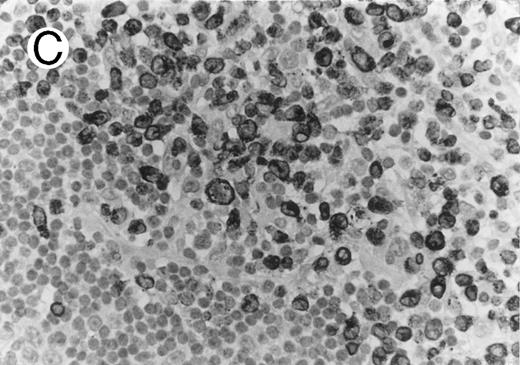

Cytotoxic granule antigen expression in a common form of ALCL (Table 2; case 11). (A) Immunostain for CD30 highlights sheets of large tumor cells. (B) The tumor cells of this case display granular cytoplasmic TIA-1 immunoreaction with paranuclear accumulation in the Golgi region. (C) Strong cytoplasmic perforin reaction is shown in the same case. (sABC-peroxidase technique, hematoxylin counterstain, original magnification × 400.)

Twenty-two ALCLs (67%) showed perforin+ neoplastic cells. Three of them were focally positive showing perforin staining in less than half of the large atypical cells. The perforin+ cases comprised 14 of 19 CS forms (74%), 6 of 6 HR (100%), and 2 of 2 SCP variant cases (100%). Perforin+ tumor cells were not detected in any of the AIDS-associated and PC cases. The perforin+ neoplastic cells showed either a dot-like paranuclear or a diffuse cytoplasmic reaction, with frequent perinuclear accumulation outlining the nuclear membrane (Fig 1). Occasionally granular staining was also present in some tumor cells. In the SCP variants, both CD30− small atypical cells and CD30+ large lymphoma cells showed perforin positivity, although the large cells displayed a more intense homogeneous reaction. Scattered non-neoplastic, perforin+ small lymphocytes, displaying a granular reaction were detected in nearly every case in uninvolved sinuses and in the paracortex, providing a convenient endogenous positive control of the immunoreaction. The perforin+ lymphocytes were generally present in much smaller numbers than TIA-1 positive reactive lymphocytes.